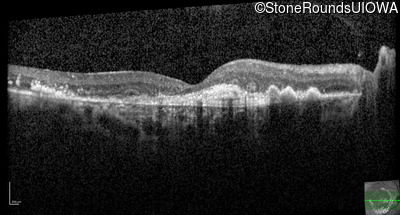

AR Stargardt Disease (IIA)

Age at visit: 59 years (Visit 3)

This 59 year old woman first noticed vision loss in her right eye a few months earlier. She has a cousin with Rhodopsin-associated RP.

Diagnosis & molecular findings

Disease Gene Allele 1 variant(s) Allele 2 variant(s) Inheritance mode

AR Stargardt Disease ABCA4 Arg219Thr AGA>ACA Gly863Ala (G)GA>(G)CA AR